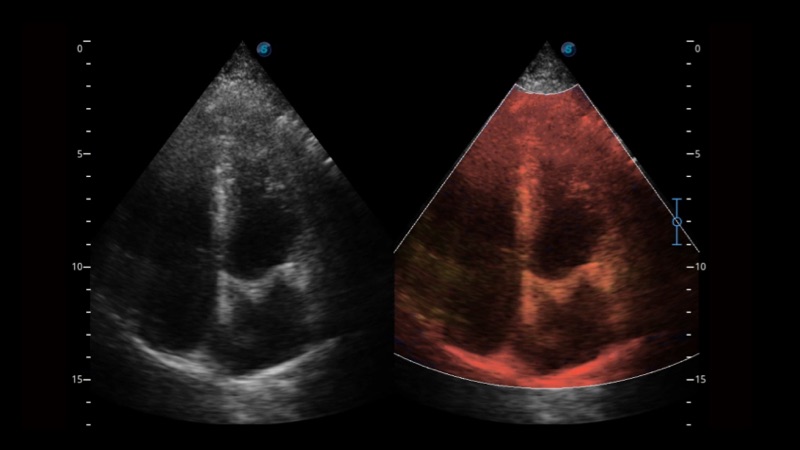

開立醫(yī)療通過不斷的技術(shù)創(chuàng)新,為大眾的生命健康提供持續(xù)關(guān)愛。P12 Plus采用全新一代超聲成像平臺,新平臺旨在將真實還原組織解剖結(jié)構(gòu)作為首要目標(biāo)。平臺采用全新集成化硬件模塊,搭載新一代芯片,系統(tǒng)性能得到大幅提升,為您的診斷提供了豐富的臨床信息。優(yōu)異的圖像表現(xiàn),豐富的探頭配置,全面的應(yīng)用功能,為您日常診斷提供了可靠的助手。

彩色多普勒超聲診斷系統(tǒng)